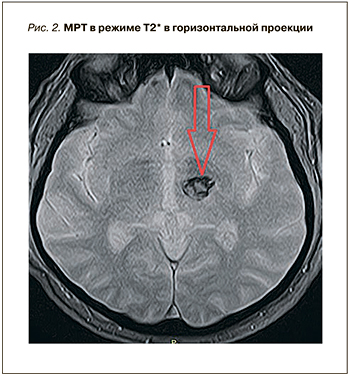

При поступлении пациенту была выполнена магнитно-резонансная томография (МРТ) головного мозга (рис. 1 и 2), на которой выявлена картина острейшего внутримозгового кровоизлияния в область базальных ядер слева (таламус) размерами до 1,8×1,9×1,8 см (объемом около 3,0 см3), без прорыва в желудочковую систему, с незначительным масс-эффектом. Отмечались очаговые изменения белого вещества головного мозга сосудистого генеза до 0,5 см в диаметре. Результаты по шкале Рэнкин составили 4 балла, по NIHSS – 5 баллов. Учитывая ясное сознание, отсутствие грубого неврологического дефицита, дислокационного синдрома у коморбидного пациента, показаний для экстренного нейрохирургического вмешательства не было. Проводилось консервативное лечение: противоотечная, гипотензивная и гемостатическая терапия. Прием ривароксабана был отменен.

При поступлении пациенту была выполнена магнитно-резонансная томография (МРТ) головного мозга (рис. 1 и 2), на которой выявлена картина острейшего внутримозгового кровоизлияния в область базальных ядер слева (таламус) размерами до 1,8×1,9×1,8 см (объемом около 3,0 см3), без прорыва в желудочковую систему, с незначительным масс-эффектом. Отмечались очаговые изменения белого вещества головного мозга сосудистого генеза до 0,5 см в диаметре. Результаты по шкале Рэнкин составили 4 балла, по NIHSS – 5 баллов. Учитывая ясное сознание, отсутствие грубого неврологического дефицита, дислокационного синдрома у коморбидного пациента, показаний для экстренного нейрохирургического вмешательства не было. Проводилось консервативное лечение: противоотечная, гипотензивная и гемостатическая терапия. Прием ривароксабана был отменен.

На фоне проводимой терапии отмечалась положительная динамика. Повторная МРТ от 28.01.2019 выявила картину подострого внутримозгового кровоизлияния в область базальных ядер слева размерами 1,2×1,4×1,2 см (объемом около 1,2 см3).